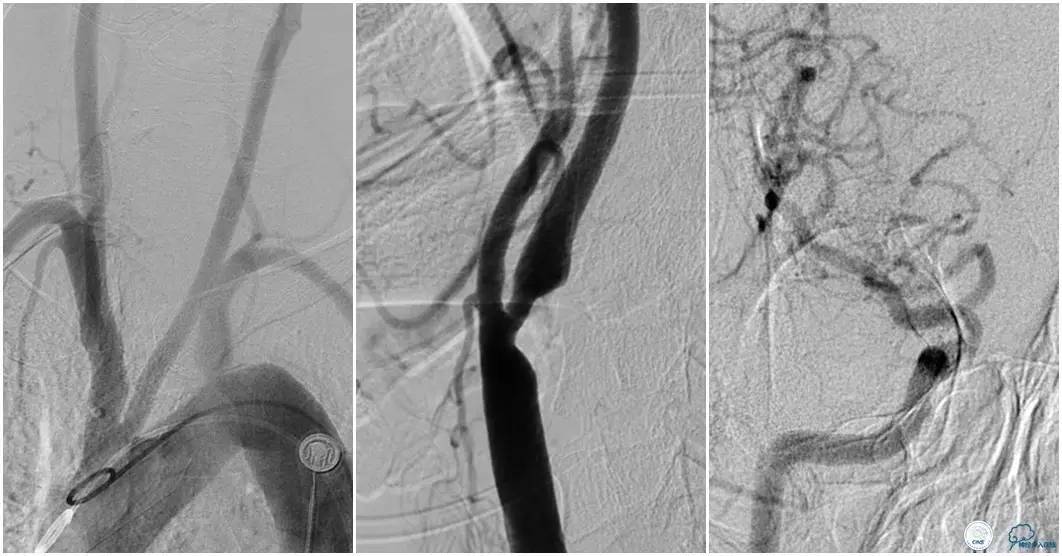

12:35穿刺成功,TOT 185min。3型主动脉弓,右侧颈内动脉起始部狭窄70%,右侧大脑前动脉A1段未显影。

双侧大脑前动脉A4段闭塞,右侧大脑前动脉由左侧大脑前动脉经前交通动脉代偿供血。

6F Envoy置于颈内动脉C3段,选用Solitaire-FR 4*20mm支架释放于右侧大脑前动脉,完全覆盖血栓。

6F Envoy置于左侧颈内动脉C3段,选用Solitaire-FR 4*20mm支架释放于右侧大脑前动脉取栓1次,血流达TICI 2b。